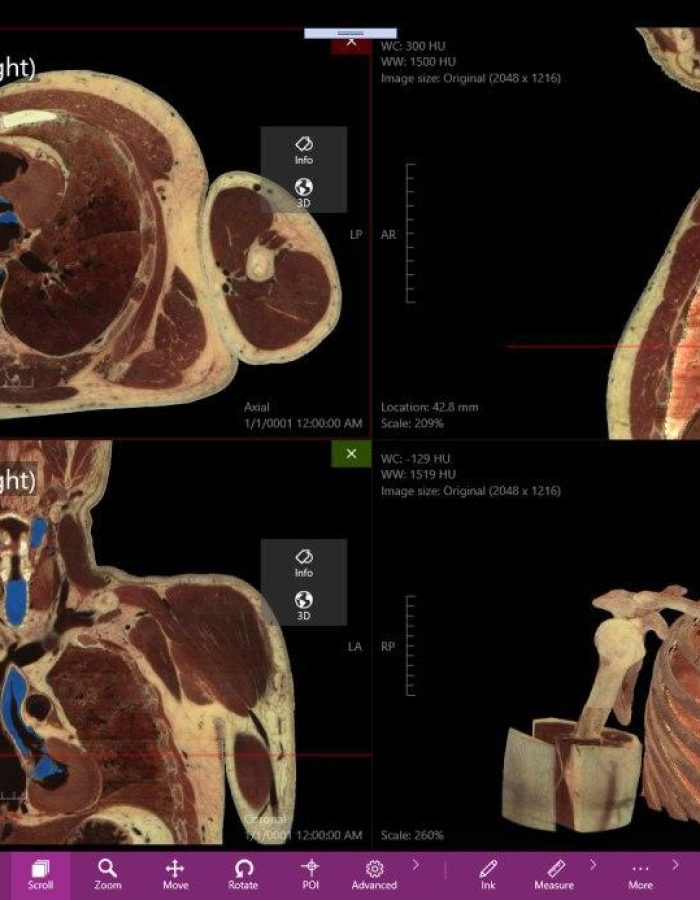

_ Amplia variedad de imágenes con un estilo profesional, tanto para estudios de casos pre operatorios como para estudio profundo de medicina.